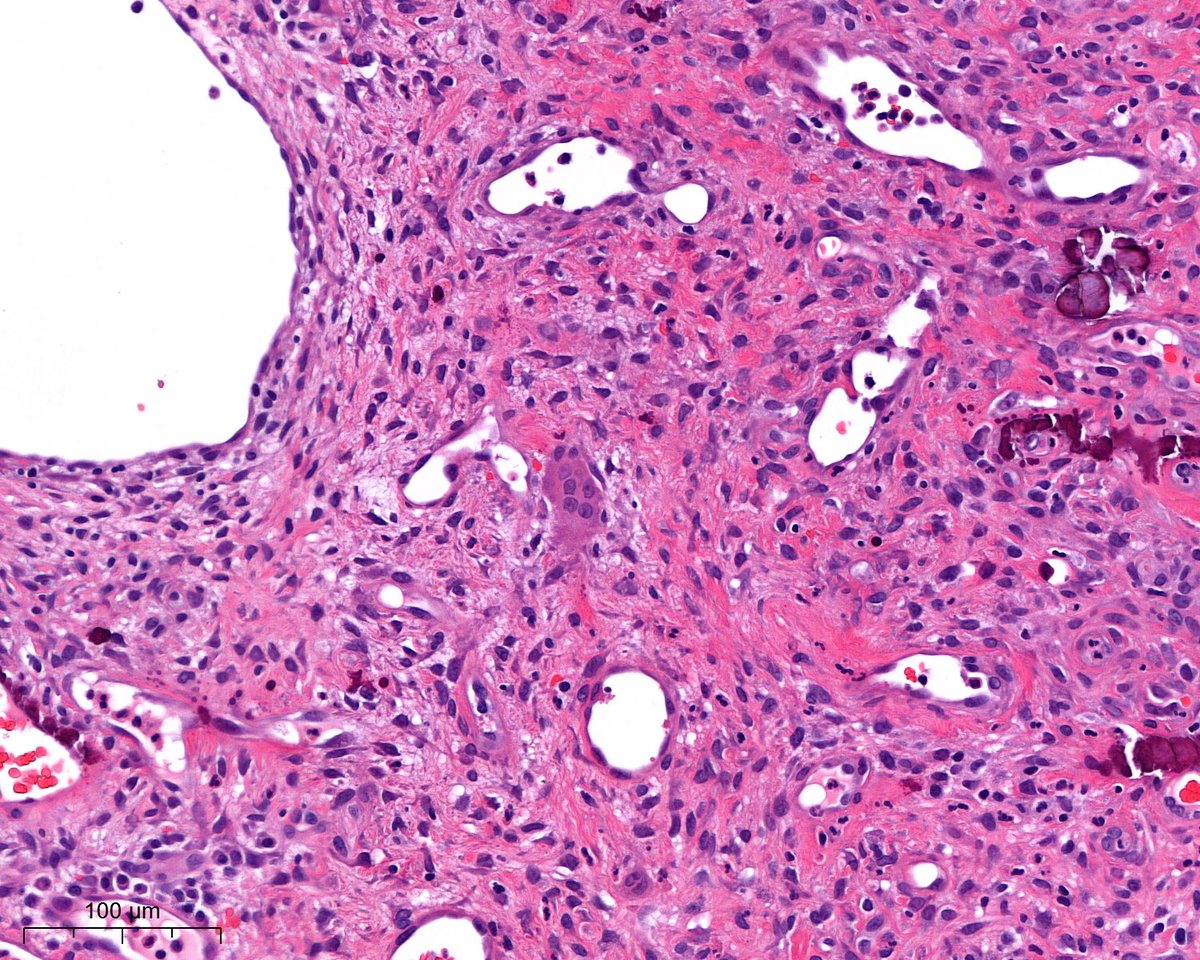

What is this? - easy; Where are we? - difficult? 😃Dr. Luca Olaleke Folaranmi Tania Labiano Aurélien Morini, MD, MSc 🇫🇷🇪🇺💙💛 Celina Stayerman MD 🔻Nusrat Zahra🔻🇵🇸 @miss_me1986 Gonzalo De Toro Tristan Rutland MBBS FRCPA IFCAP GI James Anandi Lobo, MD Angel Panizo MD, PhD 🇪🇸 🔬 Sumanta Das Lorand Kis Laura G. Pastrián MD Carlos Miguel Ruiz Carlos Nieves

benign nodule of the breast😃#breastpath Dr. Luca Olaleke Folaranmi Alexander Damron, MD Liza Quintana, MD Anne Grabenstetter Tania Labiano Jenny Pincus, MD Aurélien Morini, MD, MSc 🇫🇷🇪🇺💙💛 Celina Stayerman MD 🔻Nusrat Zahra🔻🇵🇸 @miss_me1986 Gonzalo De Toro Tristan Rutland MBBS FRCPA IFCAP Sumanta Das Israh Akhtar Khan Lorand Kis Carlos Miguel Ruiz Carlos Nieves

Out of my comfort zone case - male, late 20s, gingival tissue 😃disclaimer: pic 4 was the only giant cell present Dr. Luca Olaleke Folaranmi Nishat Afroz MD Aurélien Morini, MD, MSc 🇫🇷🇪🇺💙💛 Celina Stayerman MD 🔻Nusrat Zahra🔻🇵🇸 Amal Asar, FRCPath, MAcadMED Gonzalo De Toro Tristan Rutland MBBS FRCPA IFCAP Anandi Lobo, MD Sumanta Das Lorand Kis João Correia Pinto